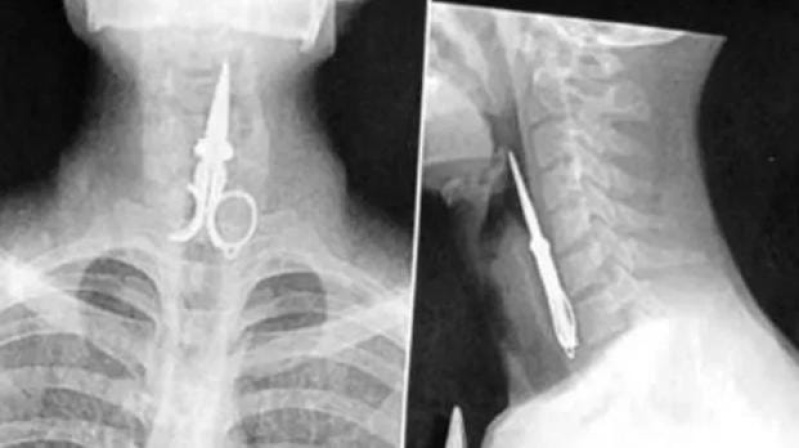

Un impensado episodio ocurrió en una cárcel de San Juan, donde un preso se tragó la mitad de una tijera como “un acto de protesta”. Se trata de Axel Hernán Rojas, que cumple condena desde 2019 por delitos contra la propiedad y ya fue protagonista de otros hechos similares en el pasado.

El suceso tuvo lugar el lunes por la noche en el penal de Chimbas, cuando Rojas, de manera deliberada, ingirió el objeto metálico. Ante la gravedad de la situación, personal penitenciario intervino rápidamente y, tras recibir la autorización del Juzgado de Ejecución Penal a cargo de Federico Zapata, dispuso su traslado a un hospital para una revisión médica.

A pesar de que el recluso se negó a recibir atención, los profesionales evaluaron su estado y determinaron que no era necesaria una intervención quirúrgica, ya que pudo expulsar la tijera por sus propios medios. Actualmente, se encuentra fuera de peligro y regresó a la cárcel.